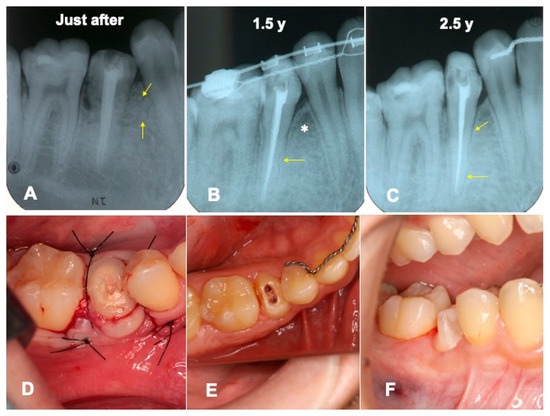

3.1. Gross View and Examinations after Surgery

3.2. Radiographic Evaluation